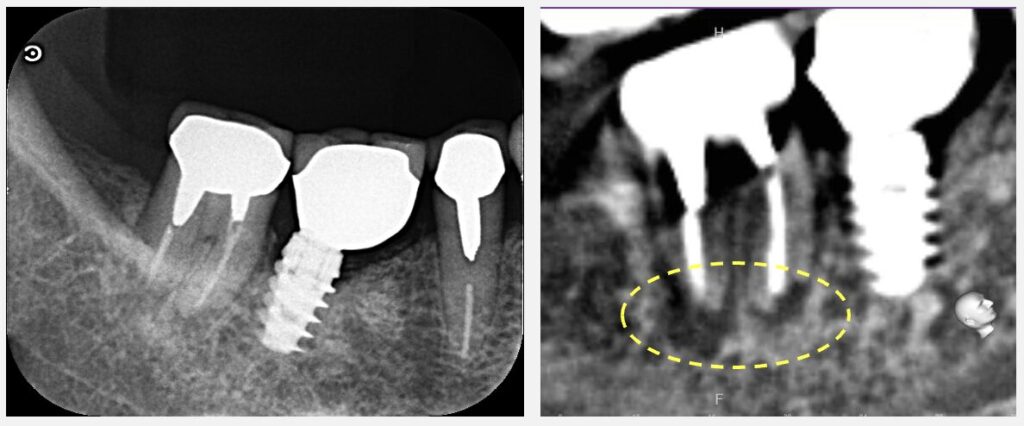

悩むところではありますが、現時点で残っている歯質がそこまでしっかりしていない可能性があります。その場合、今の古い金属修復物を外すと、歯が割れたり残存歯質がさらに減少する可能性があります。そのため、現在の歯の状態を総合的にみると、古い詰め物や金属を外さずに、歯自体を抜いて処置をする意図的再植術の適応かと思います。

ゆっくり揺らして抜くまでは少し時間がかかる可能性もありますが、術前のCT、レントゲンからはそこまで大変ではないと思います。歯を抜いてから、口腔外で処置して元に戻すまでは、概ね15分程度で完了する予定です。その間は、ガーゼを噛んでいただき、マイクロスコープで行う処置を座った状態でリアルタイムで見ていただく形になります。